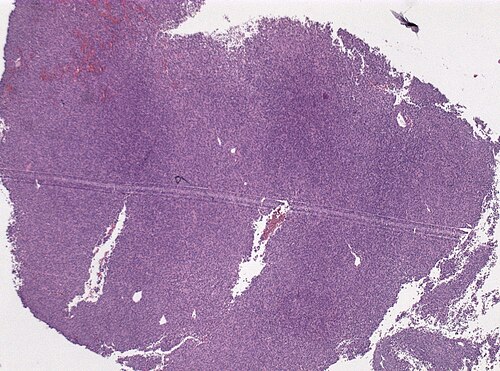

53 year old female with lumbar back pain

Lumbar spine

Low magnification. H&E stain.

The tumor is attached to the dura and has infiltrated the bone. It was bleeding intensely during resection.

Looks like a staghorn type vessel to me.